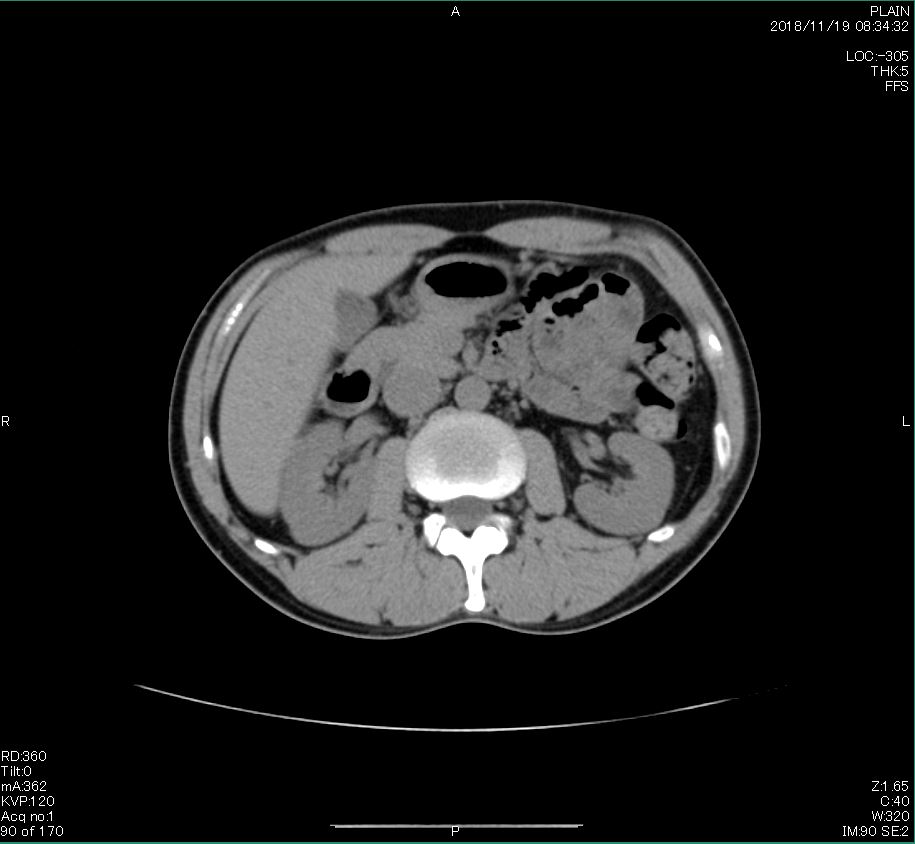

とうとうやってきた、この日が。

2006年入院治療の退院日から10年。 かなり大きな節目なんだが、なんだろうこの軽い感じは(笑)。 「10年生きたんだぁ」くらい。 変わったような変わっていないような。 当時は10年後なんて全く考えていなかった。 今も10年後は考えていないが・・・。 退院前日の2006/10/31は46.6kgだった。 今日計ったら54.8kg。体脂肪は16.6%。 とても健康にストレスなく生活できていることに、治療当時から現在に至るまで、関わった人全員に感謝の気持ちです。 マーカー、CT画像、問題なし!! 血液検査結果もほとんど文句なしの正常値。 そうだなぁ、数値に出ない異変としては、肩凝りかなぁ。 一旦夏になくなったと思ったが、初秋から再発。 マウスを左手にしたり、シップ貼ったり、最近はホッカイロ貼ったり。 で、一向に良くなる気配がない。 やはり四十肩なのか。 でも肩の可動域は問題ない。動かせないような痛みも無い。 結局色々考えてたどり着いたのは「変形性頚椎症」ではないかと。 肩凝りや頭痛がダラダラと続くようになるという症状がピッタリ当てはまる。 さて、改善策がなかなか難しい。 整形外科行ってもレントゲン撮って湿布をくれるだけだろう。 そんなことに大金を出すならまずは300円/回のプールで泳ごうと思う。 重力から開放して全身運動をするのが一番良いらしい。 2015年の目標は少しでも良いから水泳を再開する、だな。 マーカー、CT画像、問題なし!! 通常の血液検査結果も文句なしの正常値がズラ~っと並んだ!! 間違いなくヨメの食事のおかげである。ほんとうに感謝である!! ちなみに最近少々腰周りの肉付きが気になっていたのだが・・・。 左から2013年12月、2013年06月、2012年12月と背骨の位置は合わせて並べてみた。 6月まではあまり変化がなかったが、この半年で明らかに違う。 背中側の脂肪がやや増えてはいる。 でも最も大きな違いは、腸なのか、やたらと内臓が膨れている・・・。 一言で言うと食べすぎ?!?! 食事は野菜中心ではあるが、確かによく食べているw。 せっかくスーツのウエストを詰めたんだからこれ以上にならないようにしたい。 「腹八分目を心がける」かな。